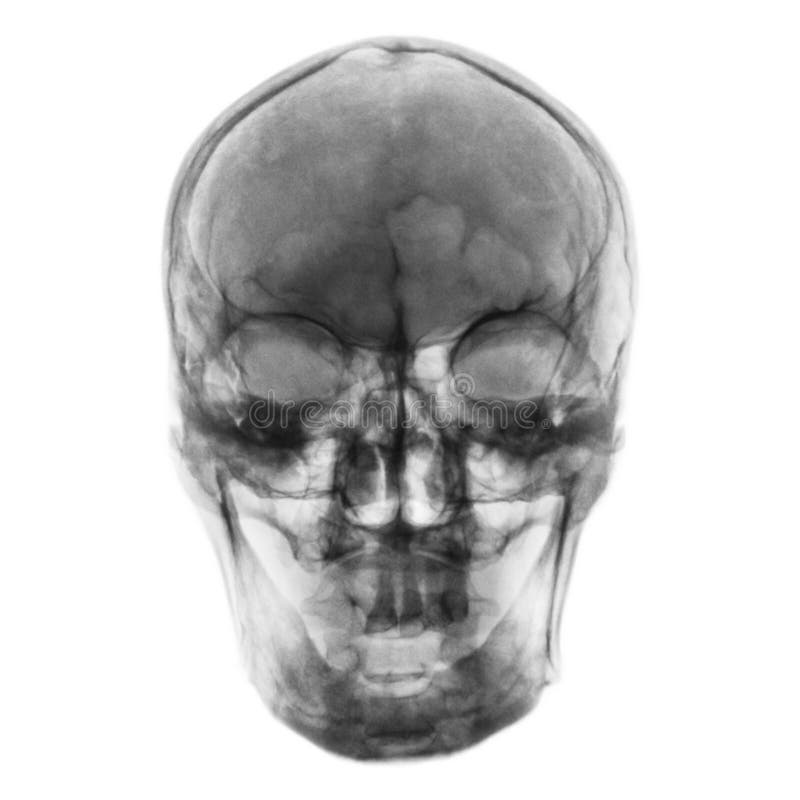

Prepare to be captivated by List, a showcase of real human skull front view black and white imagery powered by ieltschampions.edu.vn. More related visuals are below.

real human skull front view black and white

Posts: real human skull front view black and white